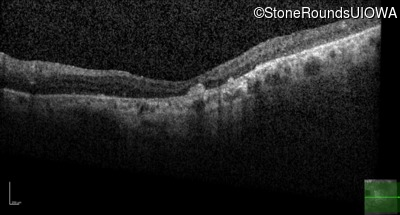

Optical Coherence Tomography - Right - 20/100

Exemplar / OCT Stack

OCT Stack

Optical Coherence Tomography - Left - 20/100